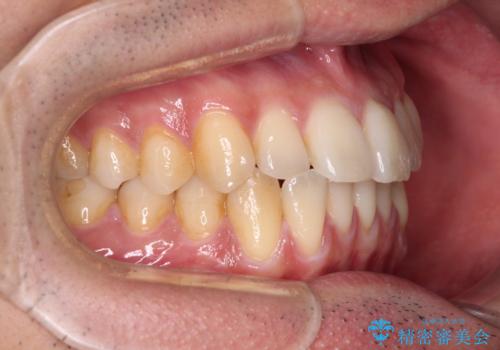

- 上下前歯のデコボコを気にして来院された患者様です。

口元の突出感や奥歯の咬み合わせに問題がなかったため、インビザラインの廉価版パッケージを用いるか上下ワイヤー装置での部分矯正を提案しました。

部分矯正は咬み合わせが不安定になったり、スペースができてしまったりと、適用となる患者様は極めて限られますが、こちらの方はスムーズに治療を終えることができました。